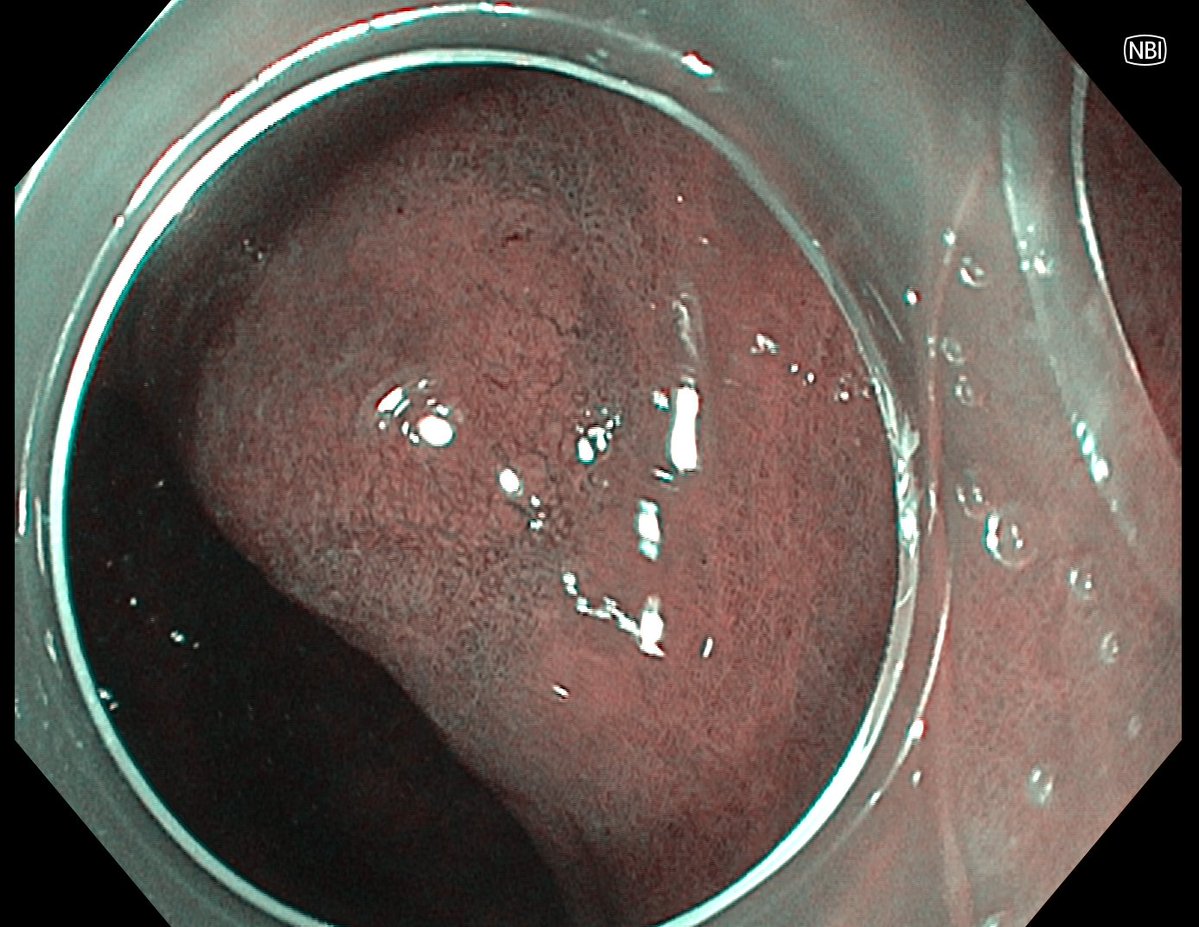

📢 March 2026 Issue #ACGCRJ 📷: Endoloop assisted hot snare polypectomy of a large brunner gland hamartoma in distal duodenum using colonoscope.🔦 🔗journals.lww.com/acgcr/pages/cu… @DushDahiya @DaniyalAbbasMD @AmCollegeGastro